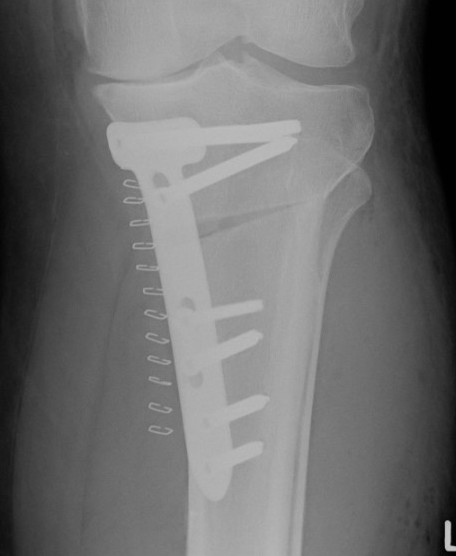

Stabilisation

- locking plates

- +/- autograft / allograft / synthetic bone graft

Arthrex Locking Puddhu plate PDF

Arthrex ContourLock system PDF